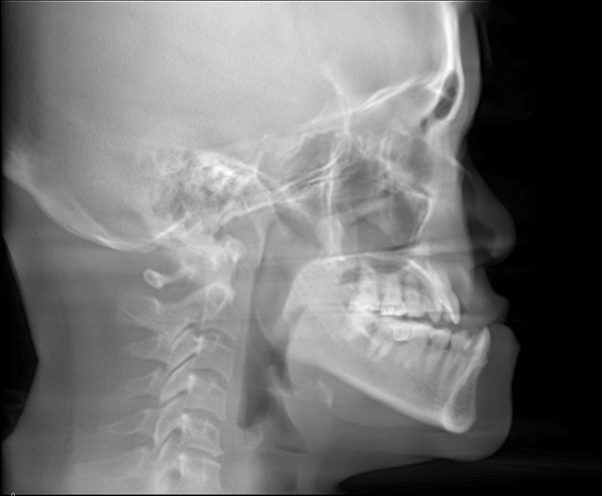

Class III malocclusion (more commonly referred to as an underbite or an anterior crossbite) affects approximately 10% of the population, where the lower jaw outgrows the upper jaw, causing the lower teeth to overlap the upper teeth